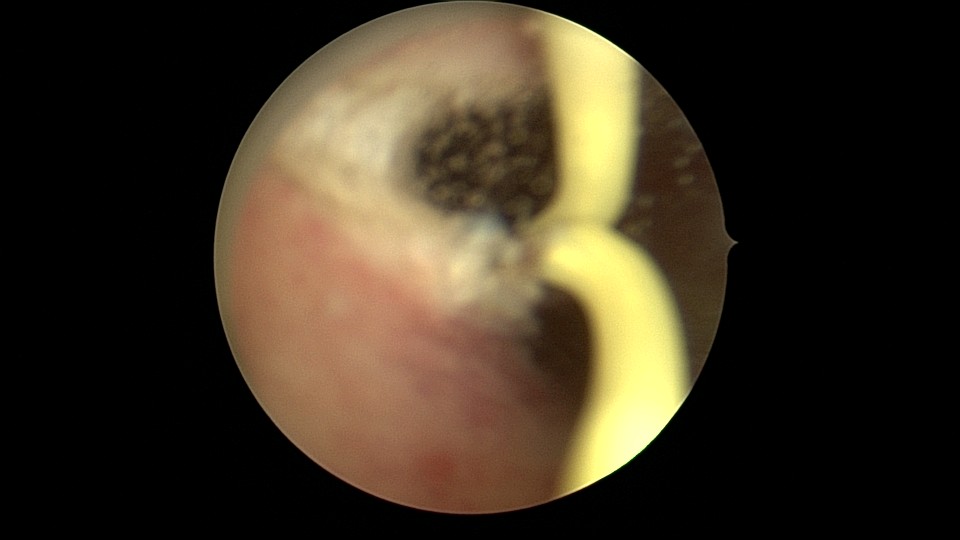

患者26岁,G7P1,剖宫产1次。2019年10月药流不全,行清宫术,术后闭经半年,后月经紊乱,周期28天~60天,月经量少。2021年4月,闭经50+天,B超提示宫腔粘连,宫腔镜见宫颈管上段封闭粘连,宫腔广泛粘连,AFS评12分(最高分)。宫腔镜电切分粘,恢复宫腔形态,显露双侧输卵管开口,宫腔防粘连复发处理,2021年5月宫腔镜二探取球囊。2021年7月自然妊娠,门诊人流并安环。2021年9月,月经推迟,B超提示宫腔粘连,节育环嵌顿,行宫腔镜取环并分粘,2021年10月二探取球囊。2021年12月放置皮埋避孕,2022年3月要求取出皮埋棒。2023年8月初自然妊娠,药流不全,2023年8月底行宫腔镜清除残留胚物。2024年2月自然妊娠10周,2024年4月初妊娠3+月(BPD2.6cm),坚决要求终止妊娠,行宫腔镜辅助终止妊娠。2025年6月因异常子宫出血再次宫腔镜分粘,2025年7月二探取球囊。现31岁,G10P1,前后共做了8次宫腔镜,术后多次自然妊娠,患者妊娠中途均选择了终止妊娠。